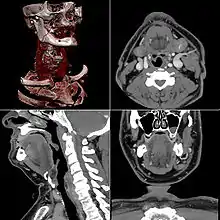

La tomodensitométrie (TDM), dite aussi scanographie, tomographie axiale calculée par ordinateur (TACO), CT-scan (CT : computed tomography), CAT-scan (CAT : computer-assisted tomography), ou simplement scanner ou scanneur pour l'appareil[alpha 1], est une technique d'imagerie médicale qui consiste à mesurer l'absorption des rayons X par les tissus puis, par traitement informatique, à numériser et enfin reconstruire des images 2D ou 3D des structures anatomiques. Pour acquérir les données, on emploie la technique d'analyse tomographique ou « par coupes », en soumettant le patient au balayage d'un faisceau de rayons X.

Dans les appareils modernes, l'émetteur de rayons X (tube à rayons X) effectue une rotation autour du patient en même temps que les récepteurs situés en face, et qui ont pour fonction de mesurer l'intensité des rayons après qu'ils ont été partiellement absorbés durant leur passage à travers le corps. Les données obtenues sont ensuite traitées par ordinateur, ce qui permet de recomposer des vues en coupes bidimensionnelles puis des vues en trois dimensions des organes. On peut faire ressortir le contraste de certains tissus, en particulier des vaisseaux sanguins, en injectant un produit dit « de contraste » (un complexe de l'iode) qui a la propriété de fortement absorber les rayons X et donc de rendre très visibles les tissus où ce produit est présent (qui apparaissent alors hyperdenses, c'est-à-dire plus « blancs » sur l'image). Grâce aux tomodensitomètres multidétecteurs (ou multi-barrettes) à acquisition spiralée (déplacement lent de la table d'examen durant l'acquisition), on obtient depuis les années 1990 une exploration très précise d'un large volume du corps humain pour un temps d'acquisition de quelques secondes.

Celles-ci se présentent sous la forme de « coupes » ou tranches d'épaisseur millimétrique (de 0,4 mm à 10 mm) que le radiologue peut étudier dans tous les plans de l'espace (sagittal, axial, coronal et obliques), et qu'il s'agit de post-traiter (augmentation de l'épaisseur des coupes visualisées, mise en valeur de certaines densités, reconstructions volumiques en 3D, extraction des vaisseaux ou des structures osseuses, navigation virtuelle endoscopique, etc.).